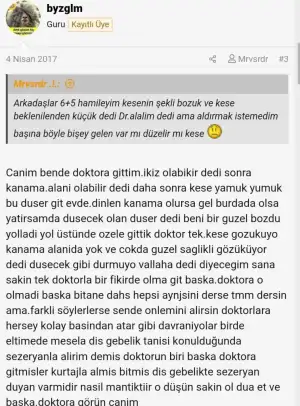

Birisi aşağıdaki gibi yorum yapmış forumda başka bir sayfada. Ayrıca başka birisine de doktoru kese şekli bozuksa kendiliğinden düşer gibi bir şey demiş. Biz bilemeyiz ama bence başka bir doktora ya da doktorlara gidip, sizin ve bebeğinizin sağlığınız için doğru olana emin olunca karar vermeniz daha doğru olur. Herkesin deneyimi farklı.Kızlar vajinal ultrason yaptı Dr smdi dış gebelik değilmiş şükürler olsun. Sağlıksız gebelik kesenin şekli bozuk dedi sadece kan sonucuma göre kürtaj yapacağını söyledi ama düzelme ihtimali vardır belki hemen kürtaj olmak istemiyorum ne yapacağımı bilmiyorum

Kimler kimler yazdı?Haklısın canım kesinlikle hemen kürtajı kabul etmeyeceğim zaten vicdanım rahat etmez yapamam bekleyeceğim tekrar başka Dr Lara’da gideceğim çok şükür dış gebelik ihtimalini atlattım en azından ona mutluyum suanBirisi aşağıdaki gibi yorum yapmış forumda başka bir sayfada. Ayrıca başka birisine de doktoru kese şekli bozuksa kendiliğinden düşer gibi bir şey demiş. Biz bilemeyiz ama bence başka bir doktora ya da doktorlara gidip, sizin ve bebeğinizin sağlığınız için doğru olana emin olunca karar vermeniz daha doğru olur. Herkesin deneyimi farklı.

Canım öncelikle gözün aydın olsun benim okuduğuö kadarıyla 8. Haftaya kadar kürtaj olmamak en iyisi sankiKızlar vajinal ultrason yaptı Dr smdi dış gebelik değilmiş şükürler olsun. Sağlıksız gebelik kesenin şekli bozuk dedi sadece kan sonucuma göre kürtaj yapacağını söyledi ama düzelme ihtimali vardır belki hemen kürtaj olmak istemiyorum ne yapacağımı bilmiyorum

Canım öncelikle gmzğn aydın dış gebelik olmaması iyi. Ama kürtaj için lütfen acele etme bi kaç doktor görüşü alKızlar vajinal ultrason yaptı Dr smdi dış gebelik değilmiş şükürler olsun. Sağlıksız gebelik kesenin şekli bozuk dedi sadece kan sonucuma göre kürtaj yapacağını söyledi ama düzelme ihtimali vardır belki hemen kürtaj olmak istemiyorum ne yapacağımı bilmiyorum